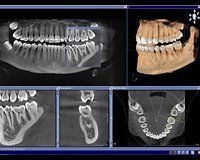

Egal ob in der Panorama-Aufnahme oder in einem dreidimensionalen Volumen, mit unserem neuen DVT sehen wir mehr und sparen Zeit bei der Befundung.

Mehr Sicherheit mit 3D

- Implantologie

- Oral- und MKG-Chirurgie

- Kieferorthopädie

- Allgemeine Zahnmedizin